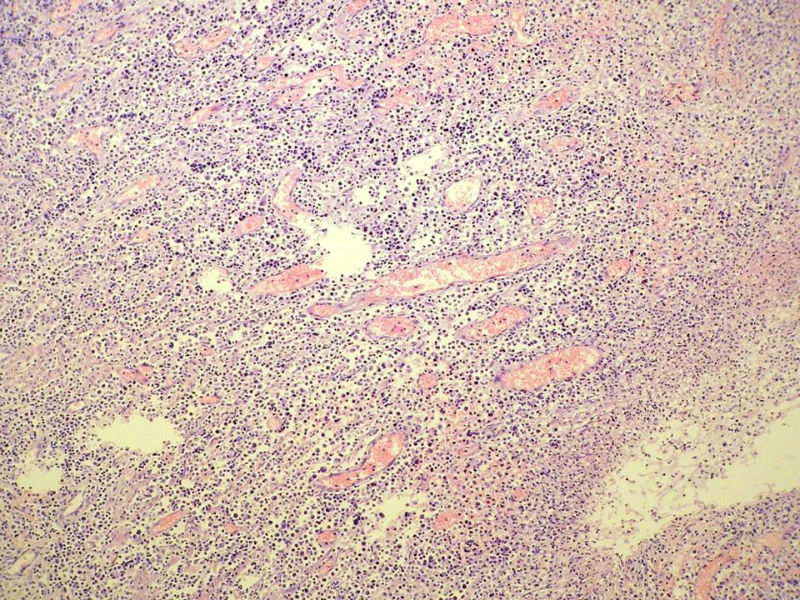

女,53岁,横结肠有9X6厘米大小溃疡,手术切除。

中老年人,溃疡很大,可见淋巴浆细胞样细胞弥漫浸润,散在大细胞,疑非霍奇颈淋巴瘤,倾向MALT伴浆样分化,不知是否破坏肌层?可否传肌层图?需IHC标记,鉴别淋巴瘤、腺癌及其它。

肉眼观仅是溃疡?有没有肠壁增厚、隆起?周围粘膜情况?肌层情况?有淋巴浆细胞样细胞、中心细胞,散在少量不成片的大细胞,不排除MALToma伴大细胞转化。

本例肉眼溃疡如溃疡性结肠炎,肠壁无明显增厚,表面辅以坏死,溃疡边缘稍隆起。镜下淋巴样细胞局限在粘膜层,肌层未见。谢谢!